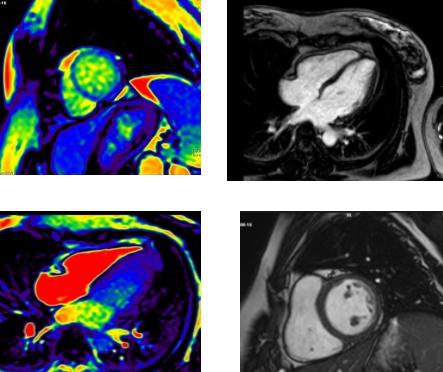

心肌致密化不全过去主要靠超声心动图诊断,但由于分辨率问题,部分患者敏感性较低,有时需要经食道UCG或心肌声学造影,心脏MRI对NVM诊断敏感性可达86%,特异性达99%。经过明确诊断,可提高患者对疾病的重视,提高医生对患者疾病的认识,为患者提供更优化的治疗措施及预后判断。